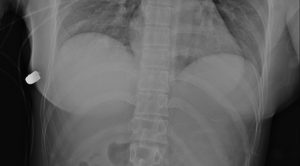

Una mujer de 30 años fue impactada por una bala mientras caminaba por una calle de Ontario, Canada, pero afortunadamente se salvó de morir gracias a sus implantes mamarios.

La mujer empezó a sentir dolor en un seno izquierdo y notó que estaba sangrando, razón por la que fue trasladada de manera inmediata a la Clínica McLean, en donde los trabajadores de salud encontraron una bala.

Los médicos aseguraron que el implante logró salvar la vida de la mujer, pues la bala iba en dirección a su corazón. Giancarlo McEvenue, cirujano plástico que retiró la bala del cuerpo de la mujer, afirmó:

“Este implante cubre el corazón y la cavidad intratorácica, así que probablemente le salvó la vida a la mujer”.

Una fractura en una costilla y daño en el tejido pulmonar, fueron las dos consecuencias que sufrió la mujer por el impacto de la bala, que podría haberla matado.

Aunque lo ocurrido pasó en el año 2018, la revista Plastic Surgery Case Studies lo hizo público hace poco tiempo.